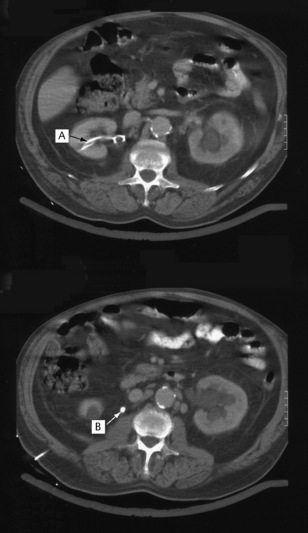

Computed tomography

Computed tomography (CT) is a quick and non-invasive technique, which can be used with or without contrast. It is used to define renal and retroperitoneal masses and is ideal for locating and staging renal tumours (Fig. 8.20). It is also used to show polycystic kidney disease and has the advantage of also highlighting non-renal pathology. Modern techniques involving spiral CT can be used to visualize the anatomy of the renal arteries, renal vein and inferior vena cava, as well as retroperitoneal studies. Increasingly, CT without contrast is the investigation of choice to diagnose obstruction to the urinary tract or renal calculi (Fig. 8.21).

image

Fig. 8.21 An abdominal CT scan of a patient who presented with acute renal failure and bilateral loin pain. There is bilateral hydronephrosis secondary to bilateral ureteric stones. In the upper image a nephrostomy tube is seen in the right renal pelvis (A). The lower image demonstrates a dense opacity (calculus) lying in the ureter approximately at the level of L2 (B). Subsequent images demonstrated a similar opacity at L3 on the left.